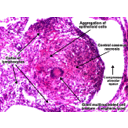

Granulome annoté.jpg